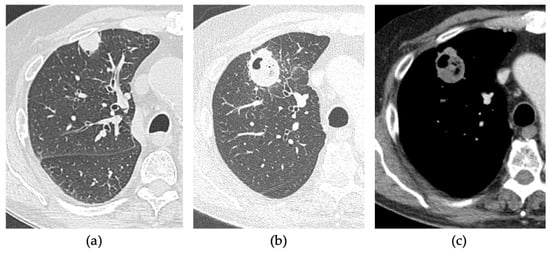

- Vespro, V.; Bonanno, M.C.; Andrisani, M.C.; Ierardi, A.M.; Phillips, A.; Tosi, D.; Mendogni, P.; Franzi, S.; Carrafiello, G. CT after Lung Microwave Ablation: Normal Findings and Evolution Patterns of Treated Lesions. Tomography 2022, 8, 617–626. [Google Scholar] [CrossRef]